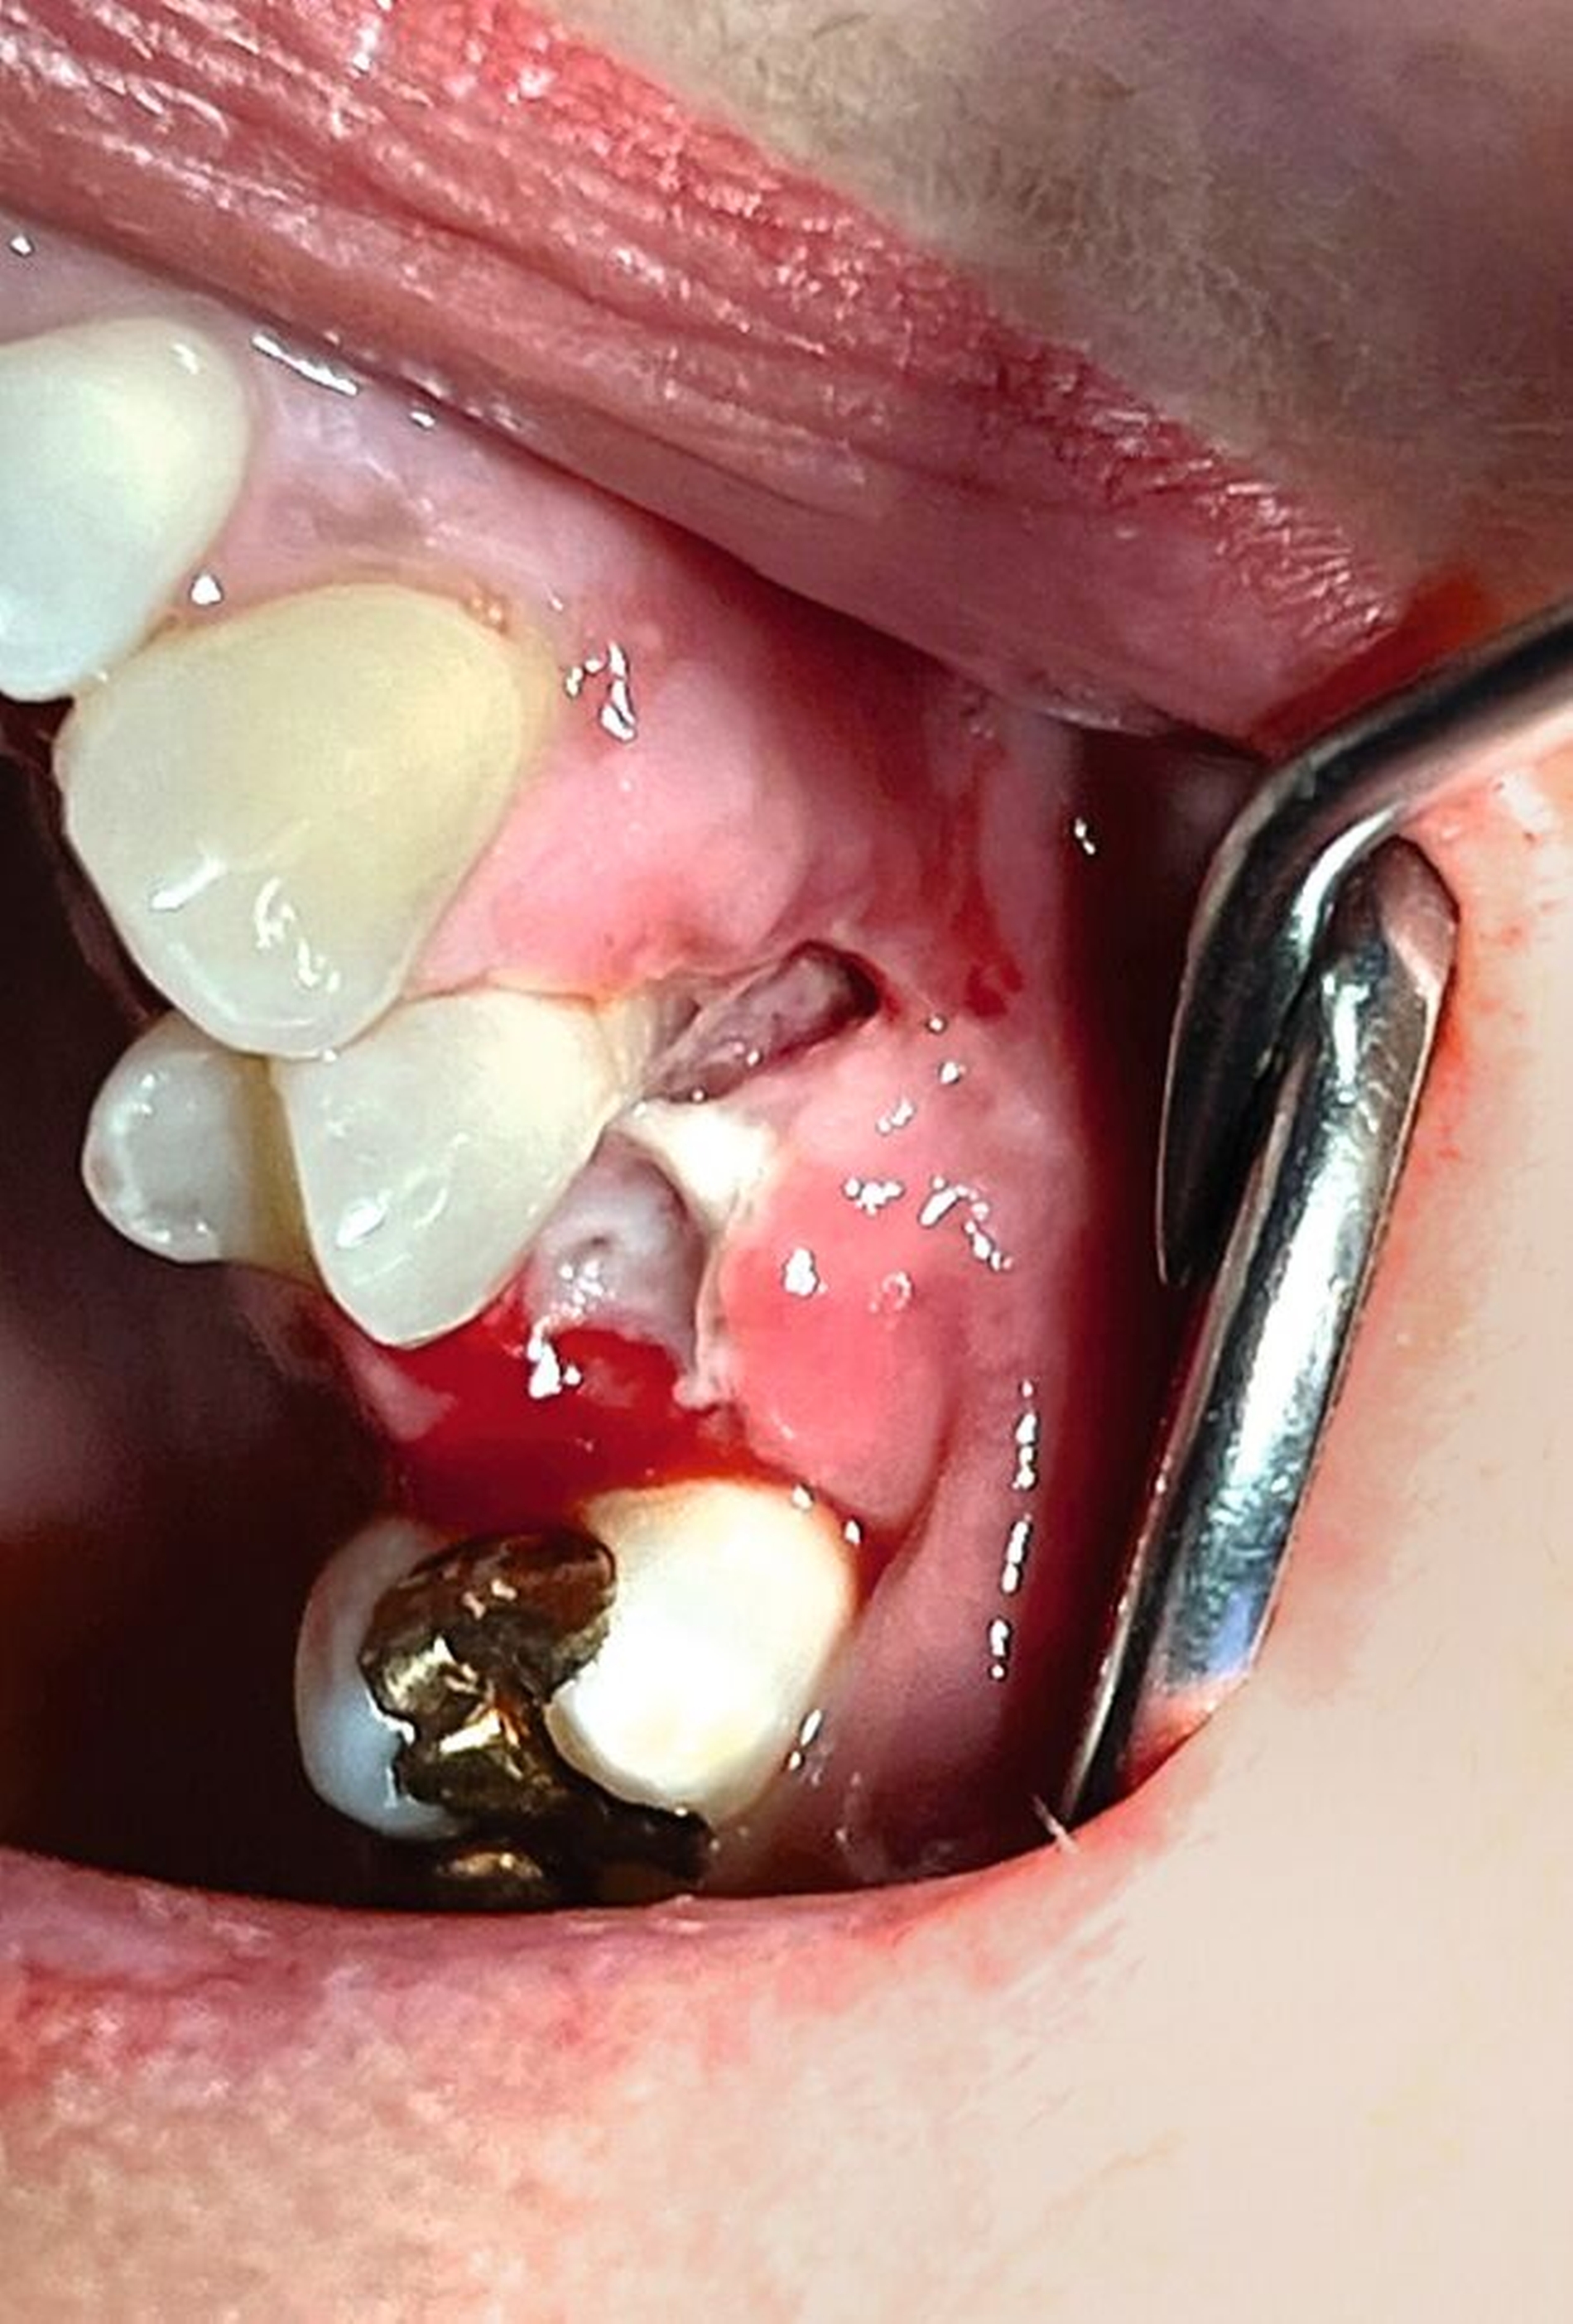

Klinisch zeigte sich derZahn 25 perkussionsempfindlich mit Lockerungsgrad II (der ja bereits vor der Wurzelbehandlung vorhanden war). Der umgebende Knochen war exponiert und nekrotisch, jedoch schmerzfrei (Abbildung 1). Der Vitalitätstest mit Kältespray ergab keine Reaktion an Zahn 24, während die Zähne 26 und 23 vital reagierten. Aufgrund der ausgedehnten Nekrose und der vorhandenen Zahnlockerung entschieden wir uns im Einvernehmen mit der Patientin für die chirurgische Entfernung des Zahnes sowie des nekrotischen Hart- und Weichgewebes. Die Patientin wurde ausführlich über die Risiken des Eingriffs (Schmerzen, Schwellung, Nachblutung, Nervverletzung, mögliche Eröffnung der Kieferhöhle, Schädigung benachbarter Strukturen) aufgeklärt und erhielt einen entsprechenden Aufklärungsbogen.

Das präoperative OPG zeigte einen generalisierten horizontalen und an den Zähnen 16 und 26 auch einen vertikalen Knochenabbau, Konkremente insbesondere im zweiten und im dritten Quadranten und in der Unterkieferfront, einen Füllungsverlust an 22, eine regelrechte Wurzelkanalbehandlung an Zahn 25, aber keine weiteren Auffälligkeiten in den umgebenden radiologischen Strukturen (Abbildung 2). Unter antibiotischer Abschirmung wurde der nekrotische Knochen einschließlich des Zahnes 25 bis zum vitalen, durchbluteten Gewebe in Lokalanästhesie abgetragen (Abbildung 3). Der Wundverschluss erfolgte mittels eines Dehnungslappens durch Periostschlitzung (Abbildung 4). Es folgte eine detaillierte Instruktion zur postoperativen Wundschonung. Eine Röntgenkontrolle wurde postoperativ durchgeführt (Abbildung 5).